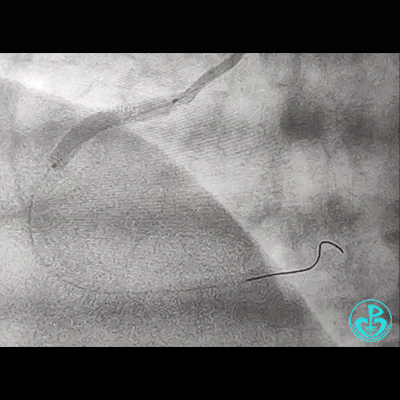

开始后扩,3.5×15mm后扩球囊不能进入近端支架口,GC系统飞出!故事开始。

重进导丝,比较顺利!3.5×15mm球囊仍不能通过支架近段!再进一根导丝,还不行!

考虑导丝可能从支架钢梁外进入,故调整GC,把两根导丝均Knuckle进入,再进球囊!不行!

因右锁骨下动脉迂曲打弯,GC张力过高,尝试GC深插,有阻力,不敢粗暴,稍微提出到开口,则立即飞出!